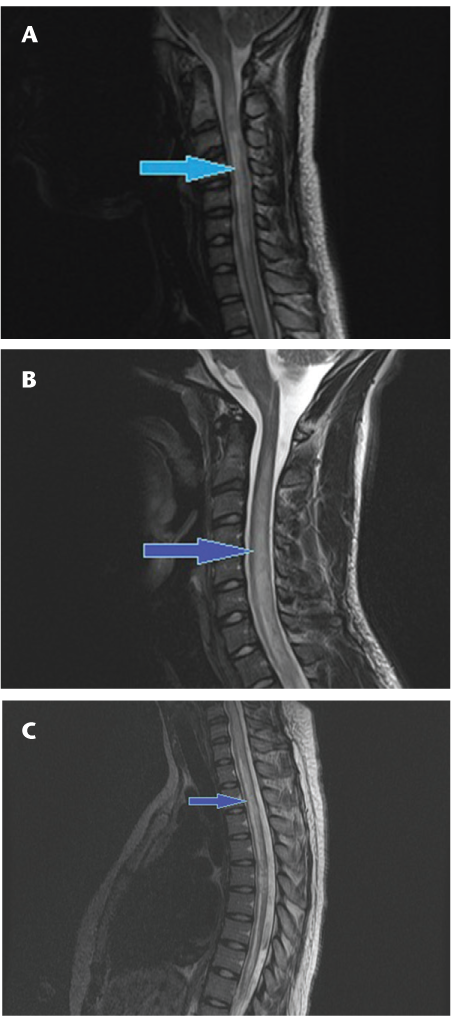

Long-segment linear T2-hyperintense lesions in the spinal cord have been shown to be characteristic of NMO myelopathy.16 17 Additionally, in our experience the typical lesions are symmetrical and centrally located in the cord (Figures 1 and 2). Those seen in MS myelopathies are usually less extensive on cross-sectional imaging and are typically asymmetrical and located at or near the periphery of the cord (Figure 3).

Sagittal T2 fast spin echo images of the cervical (A, B) and thoracic (C) spine showing continuous long-segment linear T2 signal hyperintensity (arrows) involving the spinal cord extending from the cervicomedullary junction to the T8-9 level with predominantly central involvement of the cord in a patient with neuromyelitis optica